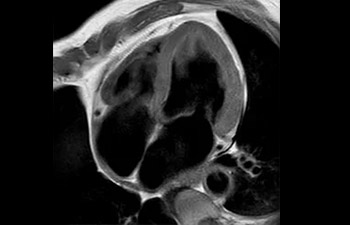

Sistema musculoesquelético

Tobillo

con Compressed SENSE